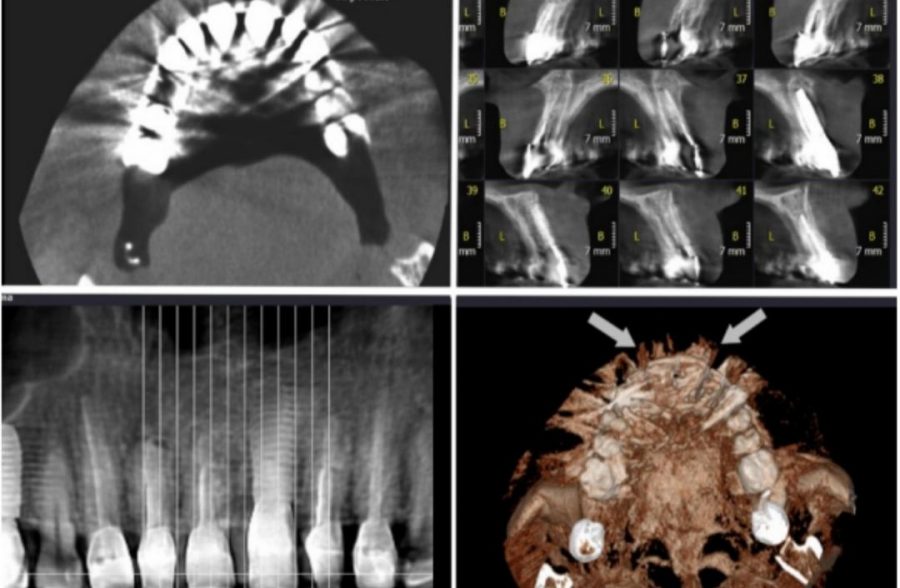

A Novel Technique for Minimizing the Metal Artifacts on Anterior Teeth in Con-Beam Computed Tomography